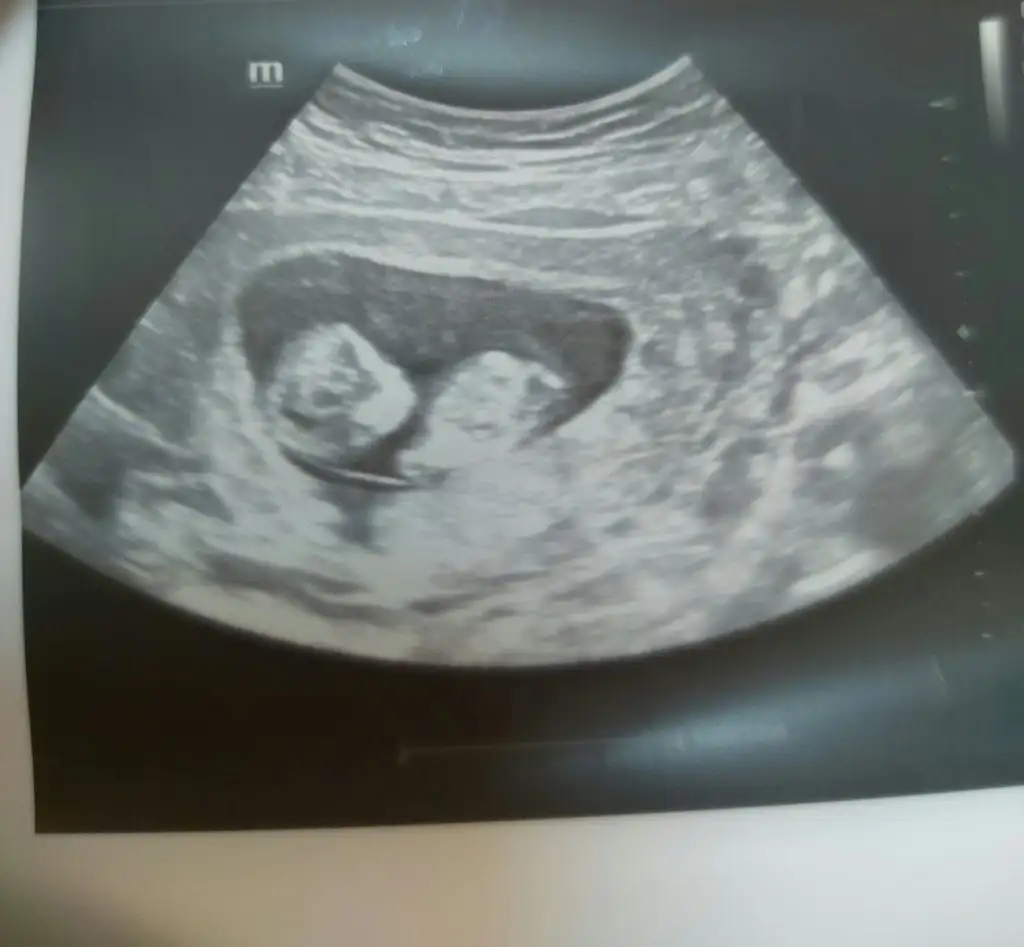

Şimdi eve gelebildim kuzum hemen yazıyorum herşey yolunda 10+1 haftalık 1 hafta geriye çekti adet tarihimi 2 li testi şansa bırakamam dedi birde detaylı ultrasonu o yüzden 14 ekime gün verdi 12+4 te 2 li taramayı yapıcaz dedi. 3.28 cm boyuYaaaaa naptın canımmmm![]()